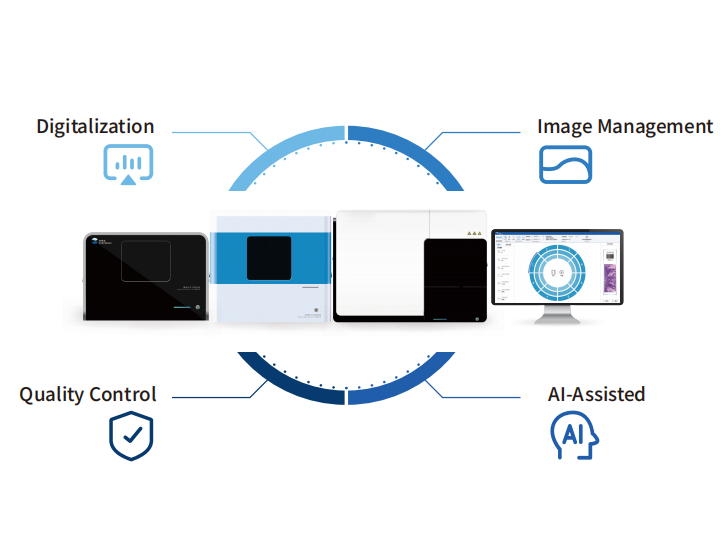

SCI-Journal Proof: AI Pathology’s Clinical Validity

Our AI-driven pathology diagnostic system has cemented its clinical credibility through rigorous research published in The Lancet Oncology, Advanced Science, International Journal of Surgery, and other premier international journals. Across dozens of SCI-indexed studies (cumulative impact factor >260, total citations >1,000), clinical data consistently demonstrate the system’s ability to solve longstanding pathology challenges with precision and reliability.